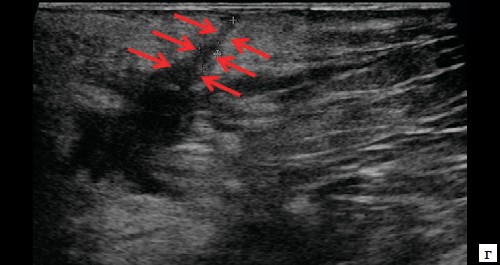

При контрольном исследовании через 3 дня после оперативного вмешательства: описываемое гипоэхогенное жидкостное образование с четкими неровными контурами с наличием неоднородного гиперэхогенного подвижного содержимого уменьшилось в размере до 2,4×1,7×1,8 см и объеме до 3,84 мл (рис. 2, а, б). В подкожно-жировой клетчатке по периферии гипоэхогенного образования отмечается уменьшение степени выраженности сосудистой реакции (рис. 2, в). Описываемый свищевой ход уменьшился в размере до 1,1×0,2×0,5 см (рис. 2, г).

Рис. 2. а, б – В-режим. Через 3 дня после оперативного вмешательства. Описываемое гипоэхогенное жидкостное образование с четкими неровными контурами с наличием неоднородного гиперэхогенного подвижного содержимого уменьшилось в размере до 2,4×1,7×1,8 см, до объема 3,84 мл (стрелки);

в – режим ЦДК. Через 3 дня после оперативного вмешательства. В подкожно-жировой клетчатке по периферии гипоэхогенного образования отмечается уменьшение степени выраженности сосудистой реакции;

г – В-режим. Через 3 дня после оперативного вмешательства. Описываемый свищевой ход уменьшился в размере до 1,1×0,2×0,5 см (стрелки).